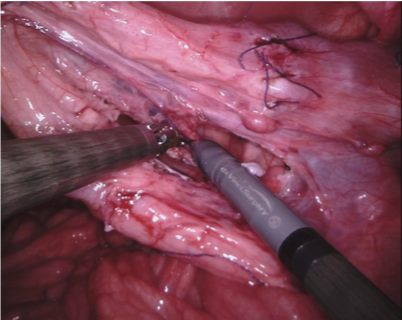

In 2017 we organized a follow-up challenge222https://endovissub2017-roboticinstrumentsegmentation.grand-challenge.org where a team at Intuitive Surgical manually segmented images from porcine robot assisted nephrectomy procedures. We aimed to improve on the previous challenge by first increasing the label quality by using hand-created labels rather than automatic labelling, secondly by adding greater variance in the background by using 10 separate procedures and finally by providing more type and part labels for the instruments.

We provided the first 225 frames of 8 sequences as training data and kept the last 75 frames of those 8 sequences as test data. 2 of the full 300 frame sequences were kept as test sequences. Test labels were kept hidden from the participants. Our datasets contain 7 different robotic surgical instruments. The Large Needle Driver, Prograsp Forceps, Monopolar Curved Scissors, Cadiere Forceps, Bipolar Forceps, Vessel Sealer and additionally a drop-in ultrasound probe, which is typically held in the jaws of the Prograsp Forceps instrument. Samples from the training datasets are depicted in Fig. 2 and examples of the different instrument types are shown in Figure 3 and 4.